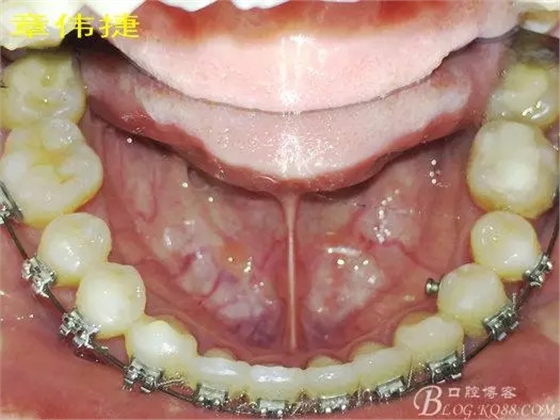

矯治八個月術(shù)中資料:

經(jīng)過8個月的治療,患者的間隙已完全關(guān)閉,患者非常滿意,后期進(jìn)入精細(xì)調(diào)整階段,建議做舌體修整術(shù),防止復(fù)發(fā)。